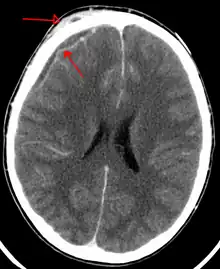

| An abscess that has led to an intracranial subdural empyema as seen on CT | |

Subdural empyema is a form of empyema – a collection of pus, in the subdural space.

Bacterial or occasionally fungal infection of the skull bones or air sinuses can spread to the subdural space, producing a subdural empyema. The underlying arachnoid and subarachnoid spaces are usually unaffected, but a large subdural empyema may produce a mass effect. Further, a thrombophlebitis may develop in the bridging veins that cross the subdural space, resulting in venous occlusion and infarction of the brain. With treatment, including surgical drainage, resolution of the empyema occurs from the dural side, and, if it is complete, a thickened dura may be the only residual finding. Symptoms include those referable to the source of the infection. In addition, most patients are febrile, with headache and neck stiffness, and, if untreated, may develop focal neurologic signs, lethargy, and coma. The CSF profile is similar to that seen in brain abscesses, because both are parameningeal infectious processes. If diagnosis and treatment are prompt, complete recovery is usual.